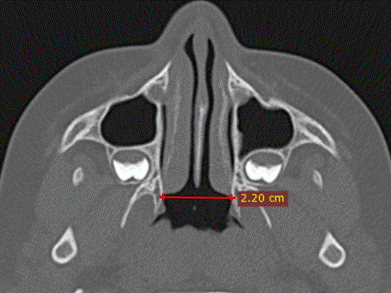

В аксиальной проекции измеряли ширину носоглотки как расстояние между латеральными точками хоан (рис. 2).

Рис. 2. КТ головы мальчика 5 лет, аксиальная проекция: ширина носоглотки.

Примечание: составлено авторами по результатам данного исследования